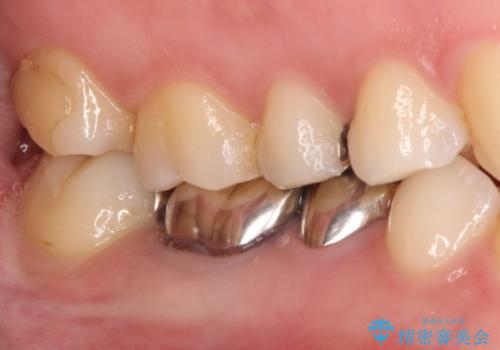

【メタルフリー】銀歯を白くしたい。オールセラミッククラウン。

- 銀歯を白くしたいと希望され来院されました。

すぐにでも白くしたいとのことで、2回目の来院で銀歯を白い仮歯に変更し喜んでいただきました。

根管治療は林先生に依頼しております。

ただ単純に白くするでけではなく拡大鏡を使用し、丁寧な処置を行なっております。